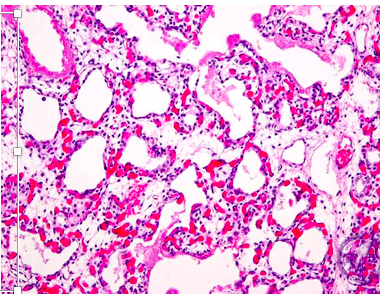

A baby is born at 26 weeks and this slide is taken from their lungs.

What has caused this?

A lack of surfactant

An infection

High oxygen tension

Pulmonary hypertension

Mechanical ventilation

A